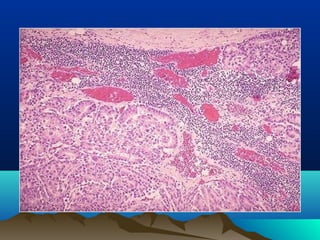

diferenciacióndiferenciación

• Es el parecido entre la célula neoplásica

transformada, con el tejido que le dio

origen, el parecido es funcional y

anatómico.

bien diferenciado: se parece al tejido que

le dio origen

poco diferenciado: no se parece al tejido

que le dio origen

• los malignos pueden ser desde bien

diferenciados a poco diferenciados o

indiferenciados

 Los tumores benignos son bien

diferenciados por definición

anaplasiaanaplasia

• La poca diferenciación de un tumor

depende de su grado de anaplasia:

• criterios morfológicos que de estar

presentes, caracterizan a un tumor como

maligno:

Criterios de anaplasiaCriterios de anaplasia

• Pleomorfismo

• Hipercromatismo

• Pérdida de la relación núcleo citoplasma

• Mitosis atípicas

• Pérdida de la polaridad